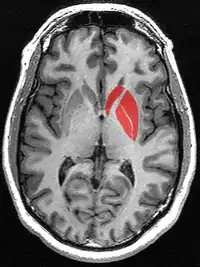

Striatum

The striatum (PL: striata), or corpus striatum[5] (also called the striate nucleus), is a nucleus (a cluster of neurons) in the subcortical basal ganglia of the forebrain. The striatum is a critical component of the motor and reward systems; receives glutamatergic and dopaminergic inputs from different sources; and serves as the primary input to the rest of the basal ganglia.

Functionally, the striatum coordinates multiple aspects of cognition, including both motor and action planning, decision-making, motivation, reinforcement, and reward perception.[2][3][4] The striatum is made up of the caudate nucleus and the lentiform nucleus.[6][7] The lentiform nucleus is made up of the larger putamen, and the smaller globus pallidus.[8] Strictly speaking the globus pallidus is part of the striatum. It is common practice, however, to implicitly exclude the globus pallidus when referring to striatal structures.

In primates, the striatum is divided into a ventral striatum, and a dorsal striatum, subdivisions that are based upon function and connections. The ventral striatum consists of the nucleus accumbens and the olfactory tubercle. The dorsal striatum consists of the caudate nucleus and the putamen. A white matter, nerve tract (the internal capsule) in the dorsal striatum separates the caudate nucleus and the putamen.[4] Anatomically, the term striatum describes its striped (striated) appearance of grey-and-white matter.[9]

The striatum is the largest structure of the basal ganglia. The striatum is divided into a ventral and a dorsal subdivision, based upon function and connections.